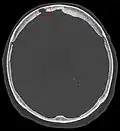

Компьютерная томограмма с грануляциями